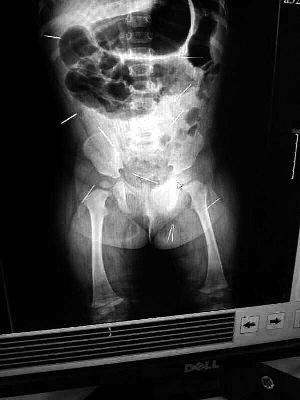

山東聊城11個(gè)月女嬰萱萱(化名)疑似被人以12根鋼針插滿臀部、腹腔等部位,昨天在兒童醫(yī)院會(huì)診后,醫(yī)生稱3根針靠近胸腔最危險(xiǎn),首批先行取出,預(yù)計(jì)將在下周二手術(shù)。孩子父母稱孩子一直由家人照顧,自家與他人并無冤怨。山東警方表示正在偵破中,不便透露案情。

“要不是當(dāng)初那幾個(gè)紅點(diǎn),可能到現(xiàn)在我們還不知道孩子身體里有鋼針!”昨天,在兒童醫(yī)院住院處,萱萱爸爸范先生稱,日前原本很愛笑的萱萱突然變得有些焦躁,一抱起來就哭,孩子母親偶然間在萱萱屁股上發(fā)現(xiàn)了幾個(gè)小紅點(diǎn)兒,原以為是蚊蟲叮咬,就醫(yī)結(jié)果卻讓人不寒而栗?!搬t(yī)院拍出的片子上,萱萱的體內(nèi)有12根鋼針,插滿臀部、腹腔、骨盆等各個(gè)部位。”范先生介紹,因?yàn)殇撫樢焉钊塍w內(nèi),要是孩子不哭鬧,他們很難發(fā)現(xiàn)。

北京晨報(bào)記者了解到,目前體內(nèi)的12根鋼針多分布在孩子的臀部,一根在腹部,其余3根在胸腔附近,其中一根很接近心臟?!耙?yàn)楹⒆犹?,醫(yī)生們害怕取針的時(shí)候?qū)λ斐蓚?,在胸腔附近?針可能會(huì)威脅她的生命”。

截至昨晚6時(shí)許,北京晨報(bào)記者從兒童醫(yī)院宣傳部門了解到,孩子目前已經(jīng)接受完專家會(huì)診,暫定今天和下周一進(jìn)行術(shù)前檢查,如果一切順利將在下周二手術(shù),“孩子暫時(shí)沒有生命危險(xiǎn)”。